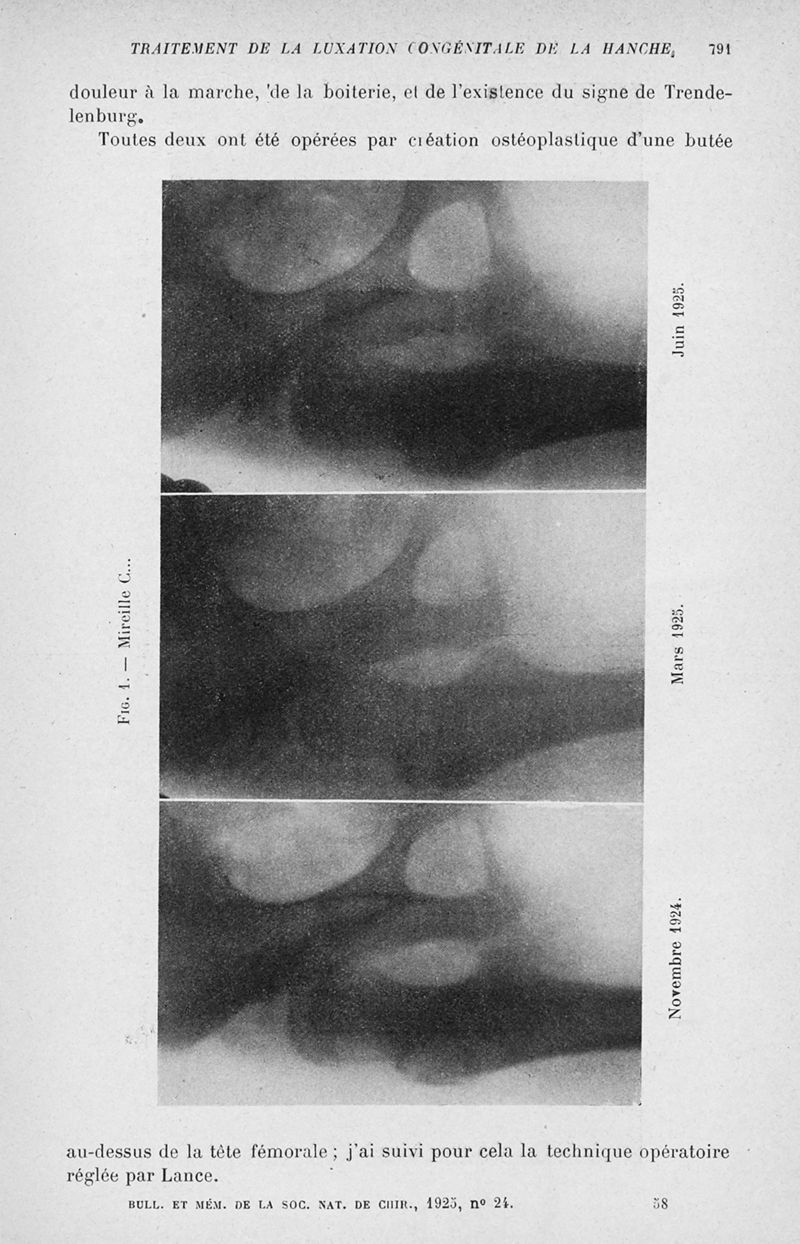

Bulletins et mémoires de la société nationale de chirurgie

Tome LI, 1925. - Paris : Masson, 1925.